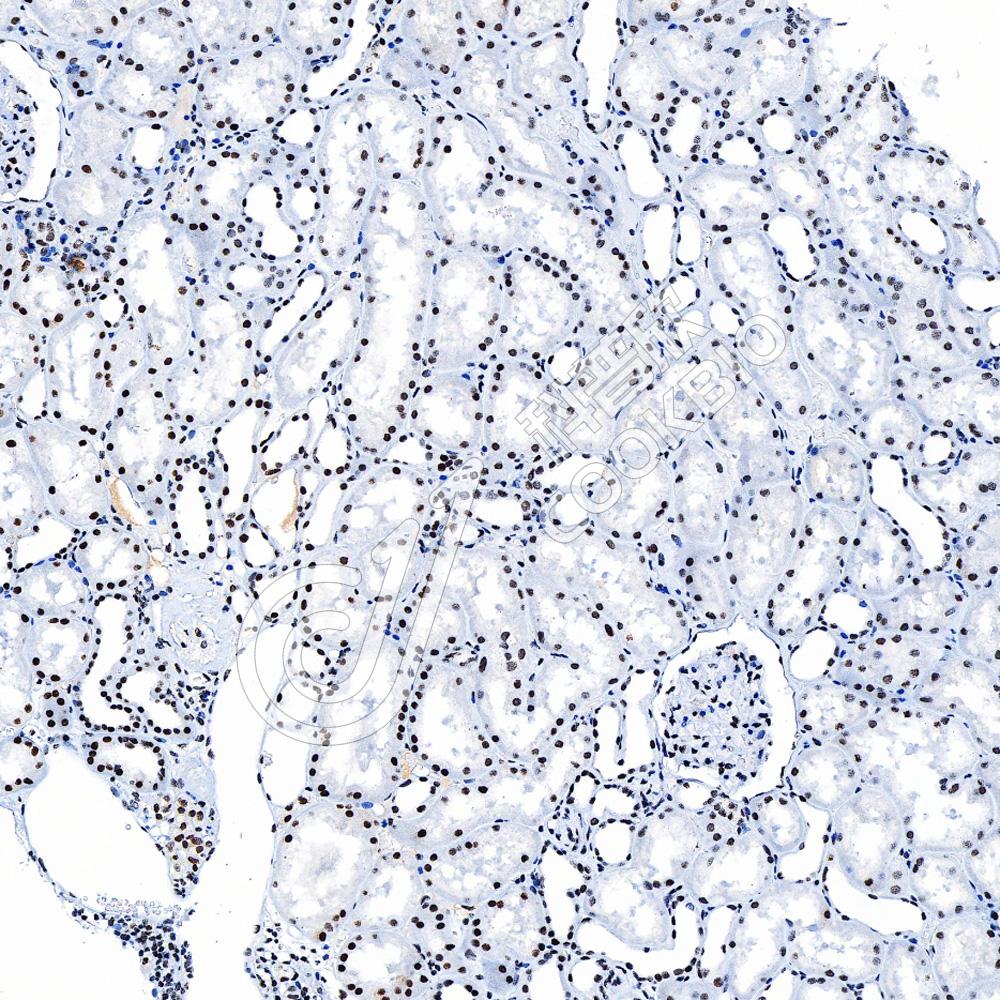

IHC检测HDAC1蛋白(货号 K545999).

样品: 小鼠肾, 4%多聚甲醛 (货号KSG1101) 固定12-24小时.

抗原修复: Tris-EDTA抗原修复液(pH 9.0) (货号KSG1203), 水浴100℃, 25分钟.

—抗: 1: 600稀释, 4℃ 孵育过夜.

二抗: S-vision免疫组化多聚二抗(山羊抗兔),即用型 (货号KB3906), 室温孵育20分钟.

样品: 大鼠睾丸, 4%多聚甲醛 (货号KSG1101) 固定12-24小时.

样品: 人肾, 4%多聚甲醛 (货号KSG1101) 固定12-24小时.